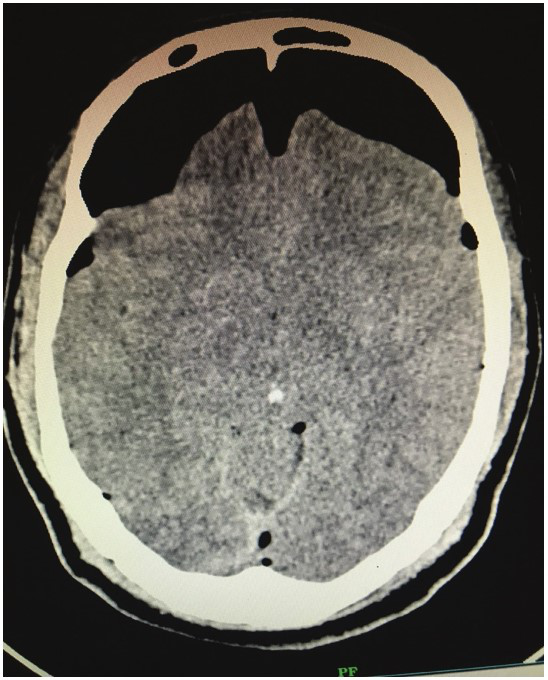

少见的颅内积气